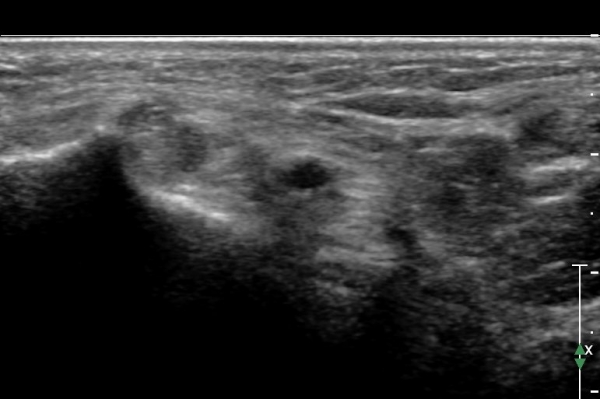

Å½ÃËÁö¸¦ Á¶±Ý ´õ ¸»´ÜÀ¸·Î À̵¿ÇÏ¿© naviculocuneiform °üÀý À§Ä¡¿¡ ¿À´Ï Knot  of  Henly °¡ °üÂûµÇ°í

À幫Áö±¼±Ù°Ç ³»ÃàÀ¸·Î  ¼ö¾×Àú·ù°¡ °üÂûµÇ°í ³»Ãø Á·Àú½Å°æÀº Ç¥ÃþÀ¸·Î  ÀüÀ§µÇ¾î º¸ÀÓ(»çÁø 4).